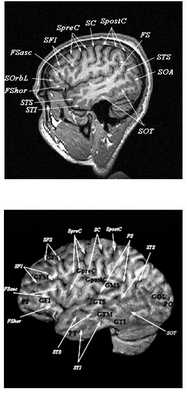

Анатомия головного мозга в МРТ изображении

МРТ головного мозга. Т2-взвешенная аксиальная МРТ. Цветовая обработка изображения.

Знание анатомии мозга очень важно для правильной локализации патологических процессов. Ещё более важно оно для изучения самого мозга с помощью современных «функциональных» методов, таких как функциональная магнитно-резонансная томография (fMRI), и позитронно-эмиссионная томография. С анатомией мозга мы знакомимся ещё со студенческой скамьи и существует множество анатомических атласов, в том числе и поперечных сечений. Казалось бы, зачем ещё один? На самом деле, сравнение МРТ срезов с анатомическими приводит к множеству ошибок. Это связано как со специфическими особенностями получения МРТ изображений, так и с тем, что строение мозга очень индивидуально.

При МРТ в СПб мы тщательно анализируем анатомию всех структур мозга пациента, что особенно важно при выявлении аномалий строения коры.

Представленная страница сайта основана на специальном изучении МРТ головного мозга здоровых лиц. Для этого изображения получали с минимальной величиной воксела (1 мм в каждом измерении), что исключало наслоения борозд. Каждая из структур прослеживалась в трёх реконструированных плоскостях путём её выделения с помощью компьютерной программы. Мы рассматривали различные анатомические варианты, что обсуждается в работе. В результате, учитывая вариабельность строения мозга, подобран условно «стандартный» мозг. Поскольку на сайте нереально представить 128 срезов в каждой из основных плоскостей, мы ограничились только каждым пятым срезом. Основные срезы в поперечной плоскости даны без наклона назад (угол 0º). Под ними для представления о изменении соотношения анатомических структур демонстрируются срезы, выполненные на тех же уровнях, но с наклонами назад -15º и -30º.

МРТ головного мозга. Объемное представление поверхности коры. Цветовая обработка изображения.

Список сокращений

Поперечные (аксиальные) МРТ срезы головного мозга

Сагиттальные МРТ срезы головного мозга